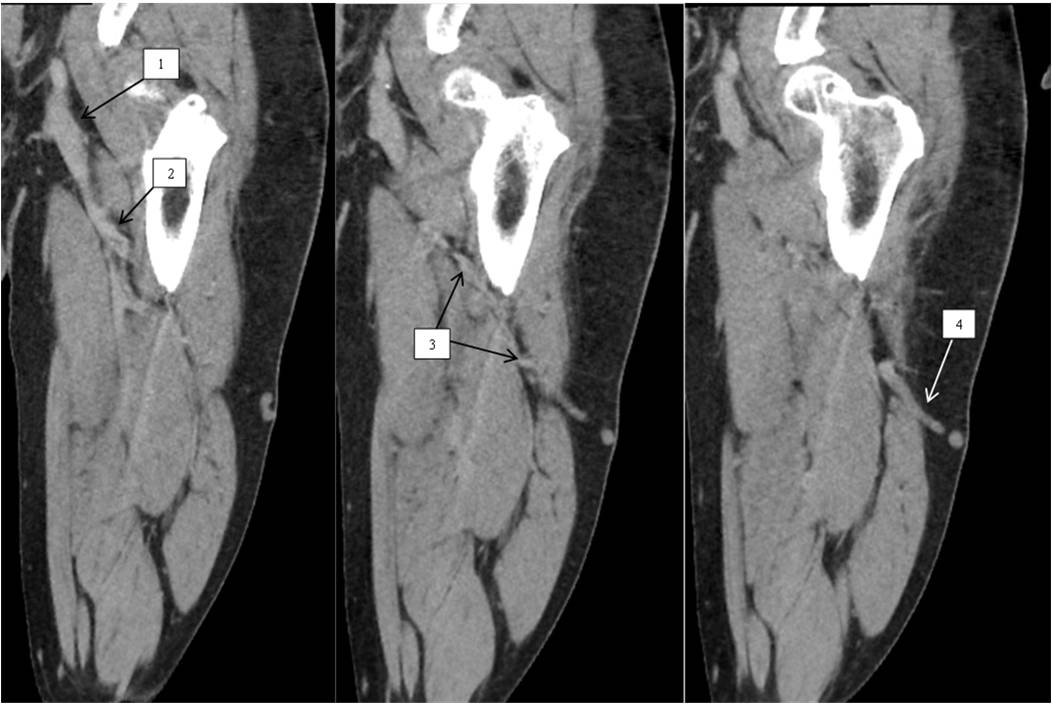

Female patient Z., 35 years old. Diagnosis: The right lower limb varicose vein disease, CEAP class C2. The disease had been present for about 10 years and was associated by the patient with pregnancy and childbirth. No edema. The volume of the right lower leg was similar to that of the left lower leg (Figure 2).

Fig. 2. Female patient Z., 35 years old. Diagnosis: The right lower limb varicose vein disease, CEAP class C2.

Notes: a black arrow — a varicose anterolateral tributary, a white arrow — the great saphenous vein orifice.

DS of the lower limb veins: deep veins patent, full compression, moderate insufficiency of the common femoral vein valves, other segments of deep veins competent. The SFJ receives the competent GSV and the varicose incompetent anterolateral tributary. SSV patent, competent (Figure 3).

CT-phlebography: deep and superficial veins uniformly, homogenously contrasted along the entire length. Varicose transformation of the saphenous vein along the lateral thigh surface. GSV, SSV without changes.

Surgery: Resection of the anterolateral tributary, miniphlebectomy of varicose saphenous veins on the thigh and lower leg. Operation report: In supine position, a varicose anterolateral tributary was isolated by a sub-inguinal access. At the site of inflow in the SFJ area, the tributary was resected, sutured, ligated. Varicose saphenous veins on the thigh and lower leg were removed using Muller hooks. Layer-by-layer suture of the postoperative wound. Treatment of the postoperative wound with iodine, application of an aseptic dressing. The postoperative period without complications. Stitches removed on the 8th day.